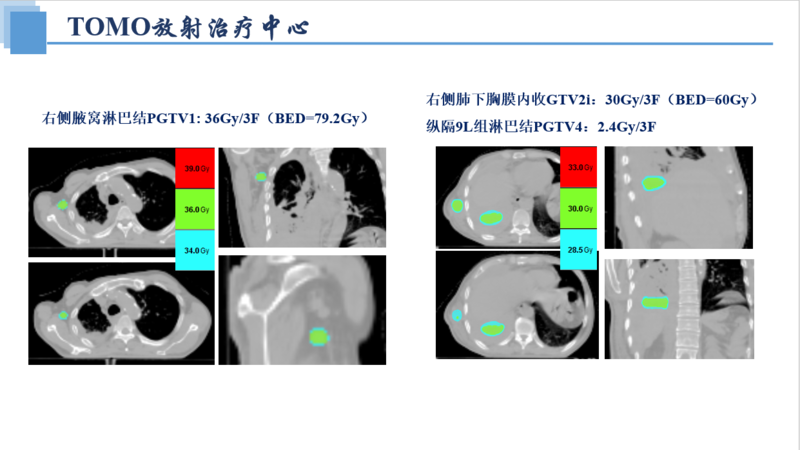

1例(男/74岁)膀胱癌多发转移(肺、骨、肝、脾、胸膜、纵隔、腹膜后、皮肤等)-TOMO放疗

郭某某(BS),男,74岁(出生时间:1949-02-01)

放疗处方剂量: